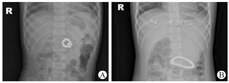

2015年1月至2020年1月收治的误食多枚磁铁异物患儿9例,其中男3例,女6例;年龄范围为1~ 4岁,发病时间为2 h至2周;主述症状以无症状为主,其次为腹痛、呕吐和发热;磁铁异物数量范围为4~25枚。本研究患儿的临床特征详见表1,典型病例的腹部立位X线片见图1。

6例经内窥镜(腹腔镜、胃十二指肠镜、结肠镜)辅助下取出异物,2例经传统开腹手术取出异物,1例保守治疗后自行排出异物,异物数目范围为4~25枚;3例术中发现多处肠管穿孔,最少2处,最多5处,1例发现胃穿孔,2例术中发现肠内瘘形成,经积极治疗后均顺利恢复,无并发症发生。9例患儿随访至今均无并发症发生。图2显示经腹腔镜辅助经脐部扩大切口拖出肠管取出异物。